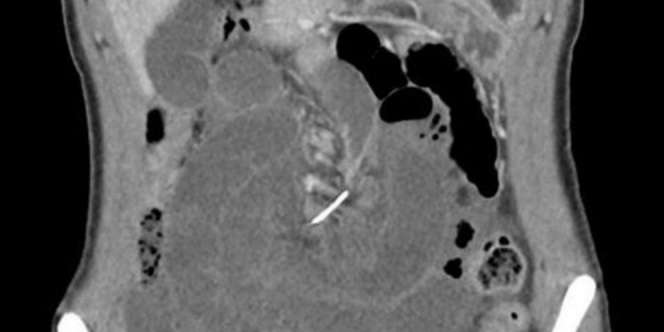

Namun, dua hari kemudian dia datang lagi dan mengeluh nyeri perut yang parah. Setelah menjalani CT Scan, dokter menemukan ada sisa kawat gigi sepanjang 7 cm yang menusuk usus kecilnya.

" Awalnya kami mengira benda asing itu adalah tulang ikan karena benda inilah yang umumnya ikut tertelan dan menancap di usus," kata dokter Shepherd.

" Ternyata benda yang menusuk usus kecilnya itu adalah sisa kawat gigi yang dia pakai 10 tahun yang lalu," kata dokter Shepherd.